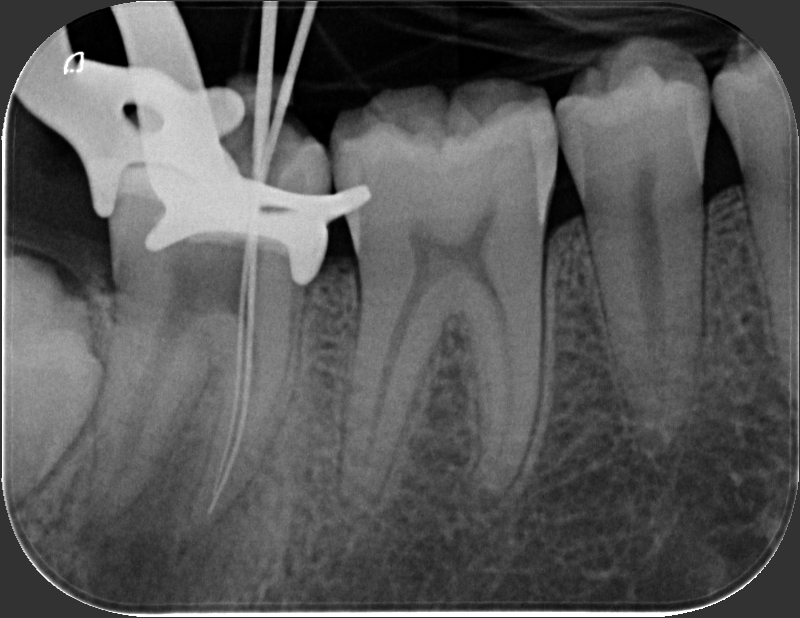

Caso clinico – trattamento ortogrado di 2° molare inferiore